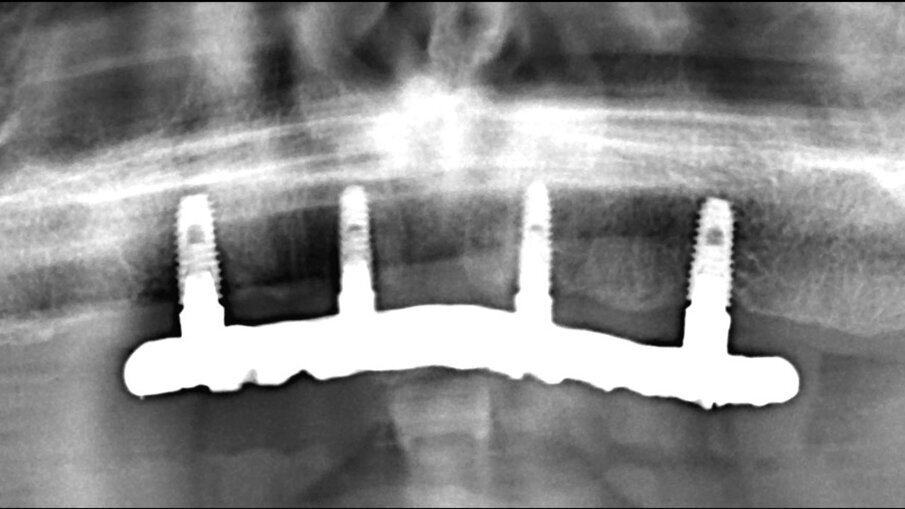

Mostriamo di seguito l’esecuzione di un lavoro di protesi ibrida su impianti tipo Toronto su sistematica OT Bridge (Rhein83, Italia). Il paziente, edentulo con più di 80 anni di età viene operato in chirurgia guidata (Figg. 11, 12). Vengono inseriti 4 impianti TSIII (Osstem, Korea) del diametro di 4 x 8.5 in zona 16, 3.5 x 11.5 in zona 12, 3.5 x 11.5 in zona 23 e 4 x 8.5 in zona 27. La progettazione è avvenuta con il software RealGuide (3Diemme, Italia) sfruttando le informazioni del montaggio dei denti della protesi totale. Nonostante la progettazione accurata, gli impianti non si sono potuti collocare in perfetto parallelismo per le condizioni ossee scarse. Quindi tra le varie fixture sono presenti disparallelismi, proprio per questo abbiamo deciso di utilizzare la sistematica OT Bridge (Rhein83, Italia) che risulta particolarmente vincente in caso di parallelismo tra i monconi. Abbiamo inserito gli abutment OT Equator (Rhein83, Italia) già al tempo della chirurgia e li abbiamo ricoperti con le viti di guarigione scegliendo la chirurgia one-stage (Figg. 13, 14).

Fig. 20_Esempio di una rx di una protesi fissa con follow-up di 6 anni. L’importanza dell’igiene oltre a tutti i fattori progettuali.